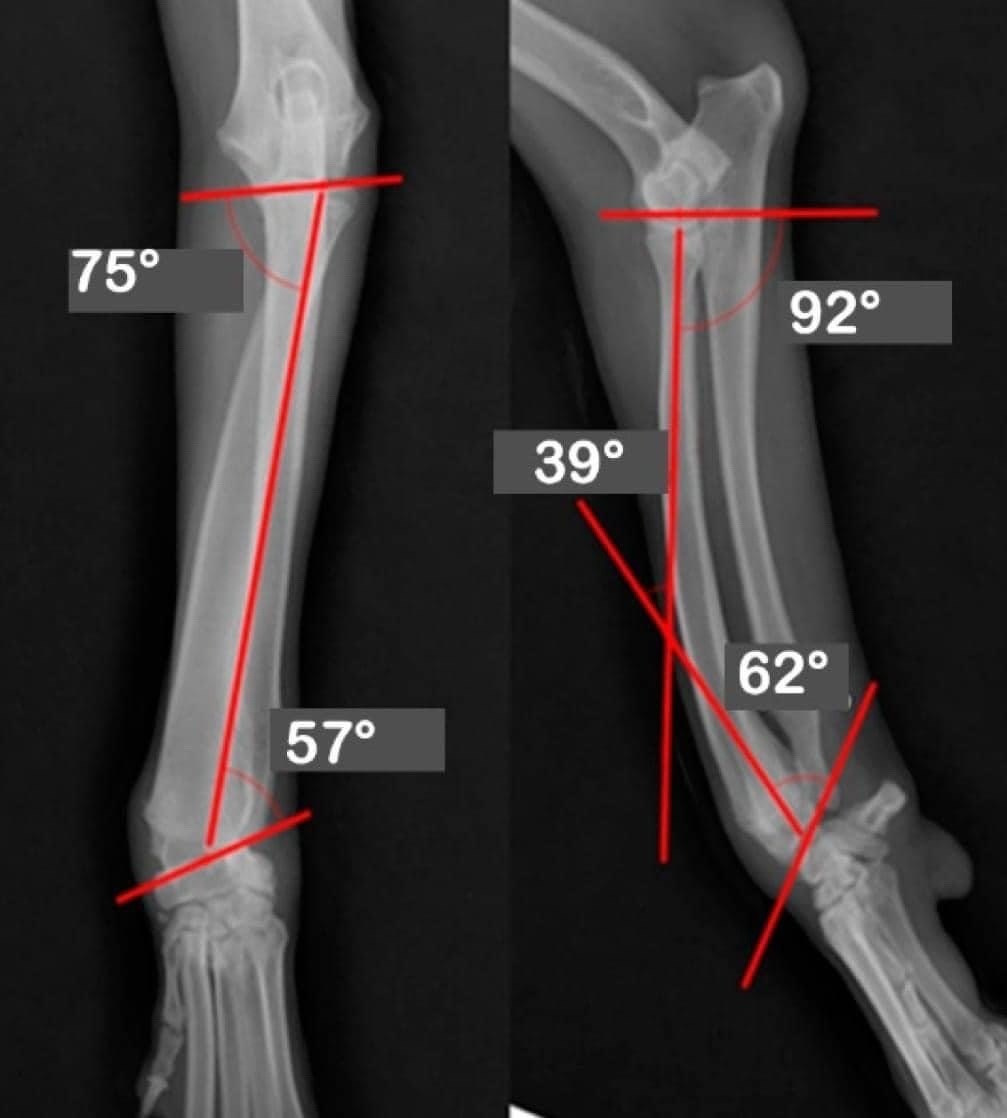

**Радио Curvo у собак: Анализ аномалий и стратегии управления**

Кривое радио, также известное как лучевая кривизна, — ортопедическая аномалия, которая влияет на структуру радиокости передних конечностей собаки. Это состояние характеризуется деформацией формы радио, представляющей себя аномальной изгибой, способной влиять на функциональность и самочувствие животного.

**Этиология Кривого Радио**

Этиология изогнутого радио может быть многофакторной. К числу наиболее распространенных причин относятся:

1. **Генетические факторы**: Некоторые расы могут иметь генетическую предрасположенность к развитию скелетных аномалий, включая радиоизкривление. Это может быть результат искусственного отбора во время размножения, где некоторые физические черты отдаются в приоритет перед другими.

2. **Недоедание и недостатки питания**: Нехватка основных питательных веществ на этапах роста может повлиять на нормальное развитие костей. Например, дефицит кальция, фосфора или витамина D может привести к деформации скелета.

3. **Травма**: Неправильные травмы или переломы в области предплечья могут привести к аномальному росту костей, вызывая нежелательную искри

4. **Патологические состояния**: метаболические или инфекционные заболевания, затрагивающие скелетную систему, также могут привести к радиодеформации.

** Функциональное и клиническое воздействие**

Наличие изогнутого радио может иметь несколько клинических последствий. В зависимости от тяжести изгиба собака может испытывать боль при ходьбе, трудности с бегом или прыжком, повышенный риск дополнительных травм. Кроме того, это состояние может изменить нормальную механику движения и предрасположить вторичные проблемы суставов, такие как артрит.

**Обработка и лечение**

Управление изогнутым радио требует многодисциплинарного подхода, включающего правильную ветеринарную диагностику и структурированный план лечения:

1. **Ветеринарная оценка**: Ветеринарный врач-ортопед должен провести тщательный физиосмотр и рентгенографические исследования для определения тяжести изгиба и оценки любых связанных с этим

2. **Хирургическое вмешательство**: В тяжелых случаях, когда функциональность конечностей нарушена, можно считать ортопедической хирургией для коррекции искривления через остеотомию (резание кости) и стабилизации внутримедулярными пластинами или ног

3. **Физическая терапия**: Послеоперационная реабилитация имеет решающее значение для восстановления нормальной функции пораженной конечности. Физиотерапия может включать специальные упражнения для укрепления окружающих мышц и улучшения подвижности суставов.

4. **Пищевая добавка**: Обеспечение сбалансированного питания, богатого важными питательными веществами, имеет решающее значение для содействия здоровому развитию костей и предотвращения

5. **Постоянный мониторинг**: Важно регулярно проводить обследования для оценки хода лечения и при необходимости внести коррективы.

Кривое радио у собак — аномалия, требующая должного профессионального ухода для обеспечения благополучия пострадавшего животного. Благодаря точной диагностике и комплексному терапевтическому подходу можно значительно улучшить качество жизни собаки и восстановить ее функциональность. Для предотвращения такого состояния у будущих поколений жизненно важно также непрерывное обучение по вопросам ответственного воспитания детей.